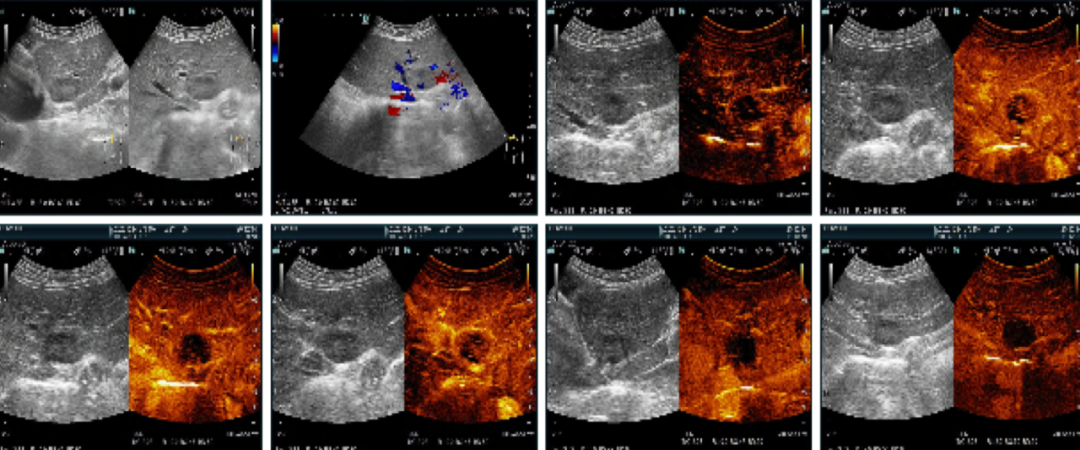

2020-10-26上腹部彩超+声学造影:肝左外叶实性结节,结合超声造影考虑Malignant(拟转移性病灶,CEUS LR- M 类)。

肝切面形态正常,肝内回声均匀,在肝左外叶可见1个肿块图像,大小约42*31mm,形态呈椭圆形,内部为低回声,内部回声分布均匀。CDFI:病灶内未见明显血流信号。超声造影:浅静脉团注1.2mL声诺维后动态观察并存储录像,肝左外叶病灶动脉期不均质稍低增强,门脉期早期、轻度廓清,延迟期病灶明显廓清,呈均匀低增强,似黑洞征。延迟期余肝扫查未见异常廓清病灶。

肝左外叶实性结节,大小约30*20mm,形态呈椭圆形,内部为低回声,内部回声分布均匀。CDFI:病灶内未见明显血流信号。结合超声造影考虑Malignant(拟转移性病灶治疗后改变,病灶较化疗前检查明显缩小,超声造影显示病灶内大部分无活性,CEUS LR- Treated)。